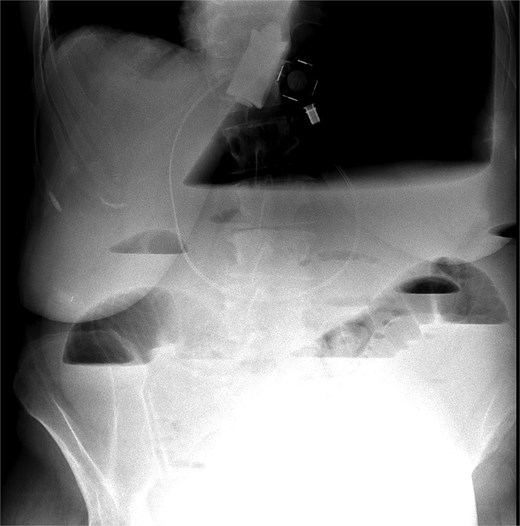

An abdominal X-ray revealed that the gastric band was in place, and there was acute massive gastric dilation, which pushed the left diaphragm up. Additionally, there was dilatation of the proximal small intestinal loops with air-fluid levels, indicating bowel obstruction (Fig. 1).

X-ray massive gastric dilatation and small bowel dilatation with air-fluid levels.